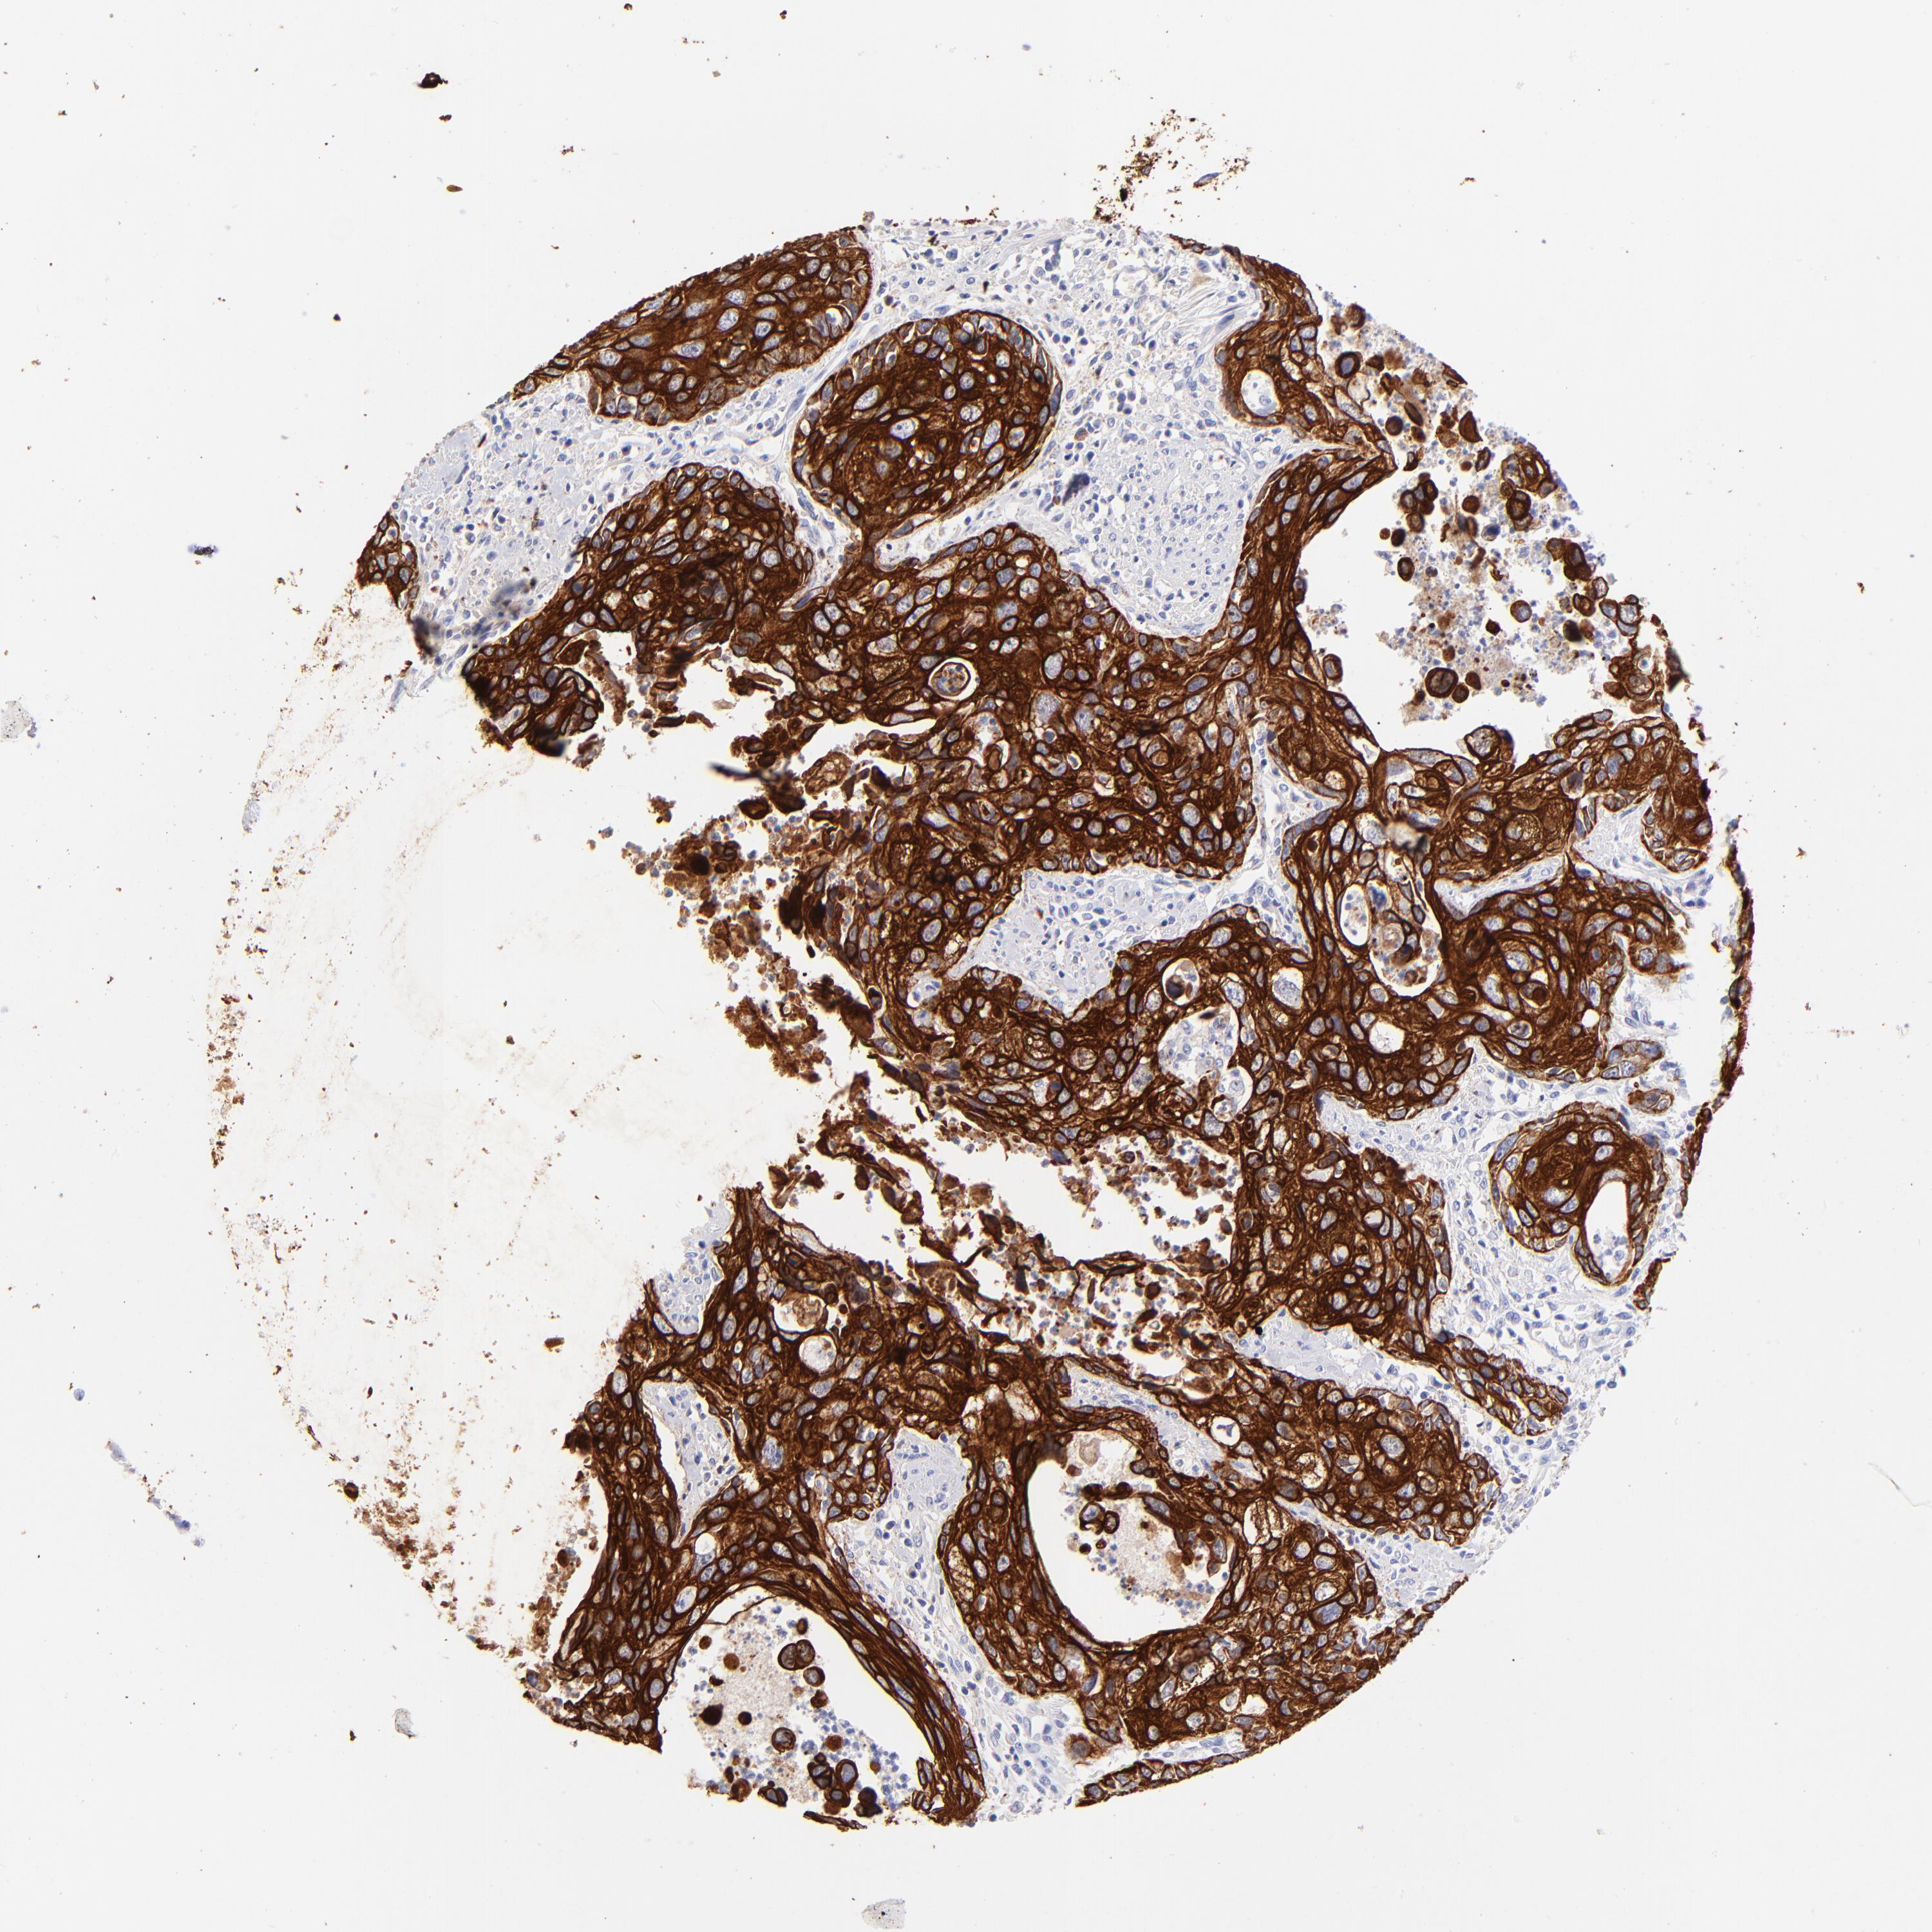

UROTHELIAL CANCER - Protein expressioni

A mouse-over function shows sample information and annotation data. Click on an image to view it in a full screen mode. Samples can be filtered based on level of antibody staining by selecting one or several of the following categories: high, medium, low and not detected. The assay and annotation is described here.

Note that samples used for immunohistochemistry by the Human Protein Atlas do not correspond to samples in the TCGA dataset.

Antibody stainingi

Antibody staining in the annotated cell types in the current human tissue is reported as not detected, low, medium, or high, based on conventional immunohistochemistry profiling in selected tissues. This score is based on the combination of the staining intensity and fraction of stained cells.

Each image is clickable and will lead to virtual microscopy that enables deeper exploration of all samples and also displays staining intensity scores, fraction scores and subcellular localization as well as patient and tissue information for each sample.

Antibody HPA002465

Antibody CAB000031

Urothelial carcinoma, High grade

Urothelial carcinoma, Low grade

Adenocarcinoma, NOS